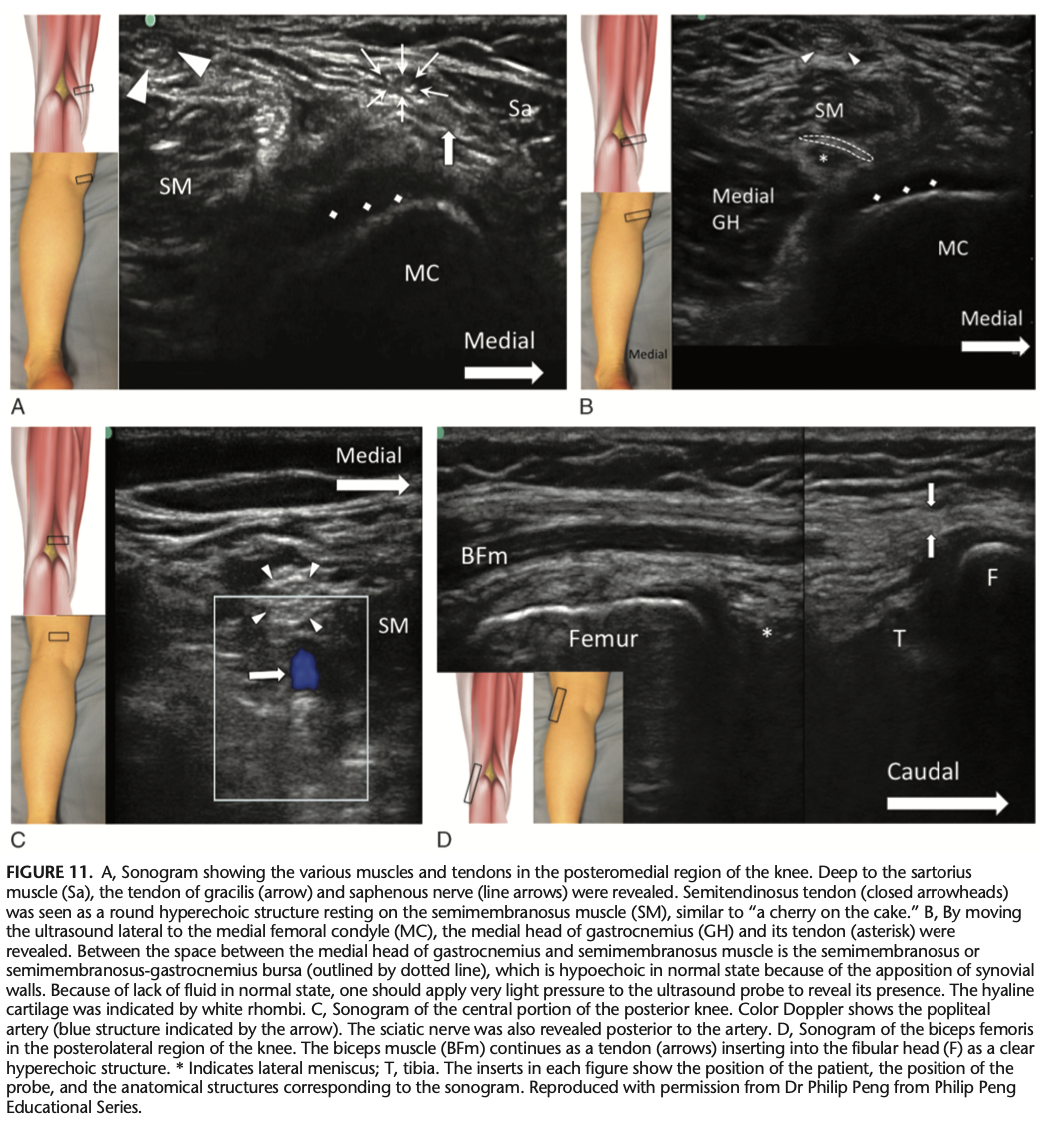

Which structures are seen from medial to lateral in the short-axis scan of the posterior knee?

A

Sartorius, gracilis, semimembranosus, semitendinosus, and medial head of gastrocnemius muscle.

Q

What is located between the tendons of semimembranosus and the medial head of gastrocnemius?

Semimembranosus or semimembranosus-gastrocnemius bursa.

What does the short-axis scan of the popliteal fossa reveal?

Neurovascular bundle and sciatic nerve (arrowheads).

What is examined in the long-axis scan when moving the probe laterally in the posterior knee?

Biceps femoris muscle and tendon.